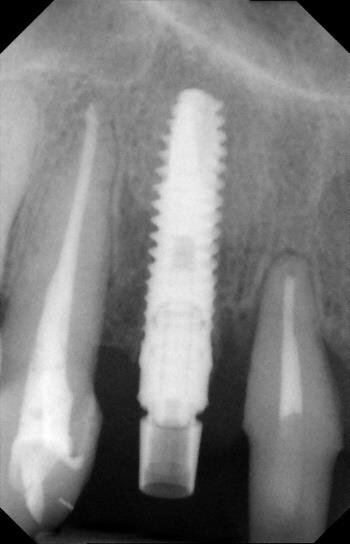

La fase chirurgica viene pianificata con la preparazione iniziale (igiene orale, controllo emato-chimico delle condizioni della paziente, prescrizione della profilassi/terapia antibiotica19-20 e della sospensione del fumo). Il 23 giugno 2011, vengono estratti i due incisivi laterali (Figg. 13, 14) e inseriti contestualmente due impianti Xive (Dentsply) di diametro 3,8 mm e lunghezza 15 mm (Figg. 15, 16), dimensioni ottimali per la successiva protesi (ponte di 4 elementi da 1.2 a 2.2 con 1.1 e 2.1, elementi “intermedi”).

Vengono inserite due viti di guarigione e riposizionato il provvisorio, debitamente adattato in corrispondenza dei due incisivi laterali. Alla seduta di controllo a una settimana dall’intervento implantare, la paziente confida, alle assistenti dello studio, di non aver assunto gli antibiotici prescritti né prima né dopo l’inserimento degli impianti e tantomeno di essersi astenuta o limitata dal fumo di sigarette! Alla seconda visita di controllo, dopo 30 giorni, la stessa presenta un pessimo stato di igiene orale e due ascessi vestibolarmente ai due impianti (1.2 e 2.2) (Figg. 17, 18).